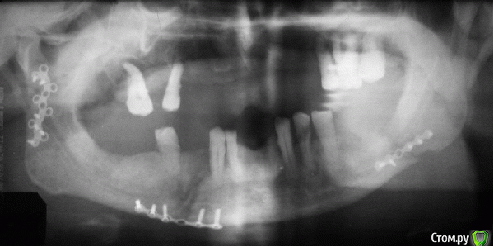

an_ver Опубликовано 11 марта, 2015 Поделиться Опубликовано 11 марта, 2015 Товарищ обратился с вопросом. Пациенту делали в Беларуссии,он его еще не видел,только снимки. Это какие импланты? Радикс? И времянки поставили? http://s017.radikal.ru/i400/1503/97/c7a30103e726.png1.bmp Ссылка на комментарий

Kovalov Igor Опубликовано 11 марта, 2015 Поделиться Опубликовано 11 марта, 2015 импланты от Biomed gcsДентальные имплантаты GCS® системы Allfit® изготавливаются из титанового сплава Ti6Al4V ELI высокой устойчивости к разрывам в соответствии с ASTM F136. Цельные имплантаты оснащены компрессионной резьбой в апикальной части и монолитным абатментом (прямым, гибким или угловым). Подходят для коронок, мостовидных протезов и балочных конструкций. Дизайн компрессионного винта позволяет осуществлять немедленную установку протеза, при условии правильного выполнения имплантации (установка реставрации в течение не более трех дней). это я из сайта вырезку взял... швейцарские импланты, Стефан Идэ приезжал в наш город, ходил на его курс...как то не внушили доверие. ставят их одномоментно, на третий день коронки уже ставят ... Ссылка на комментарий

Фарид Расулыч Опубликовано 11 марта, 2015 Поделиться Опубликовано 11 марта, 2015 Базальщина? нет? похоже очень 1 Ссылка на комментарий

syrovovec Опубликовано 11 марта, 2015 Поделиться Опубликовано 11 марта, 2015 точно не Radix,на ИОЛ похожи,но скорее всего базальщина, на ROOT похожи Ссылка на комментарий

parallax Опубликовано 11 марта, 2015 Поделиться Опубликовано 11 марта, 2015 Коллеги, это - ROOTT compressive. Ссылка на комментарий

LEOnchik Опубликовано 2 апреля, 2015 Поделиться Опубликовано 2 апреля, 2015 Это имплантанты разарботанные проф Стефаном Идэ (Stefan Ihde ) компании Ihde Dental называются комрессоинными (со Стефаном знаком лично -уникальный доктор)))). Базальными они не являются. Первичная стабилизация имплантантов происходит за счет компреммирования спонгиозной кости. Можно нагружать немедленно в случае сегментарных работ, в случае одиночных реставраций нагружать немедленно не рекомендую. Длинные импланты напоминающие шурупы- это полированные базальные импланты, некоторые их называют бикортикальными.На самом деле интересная методика! 2 Ссылка на комментарий